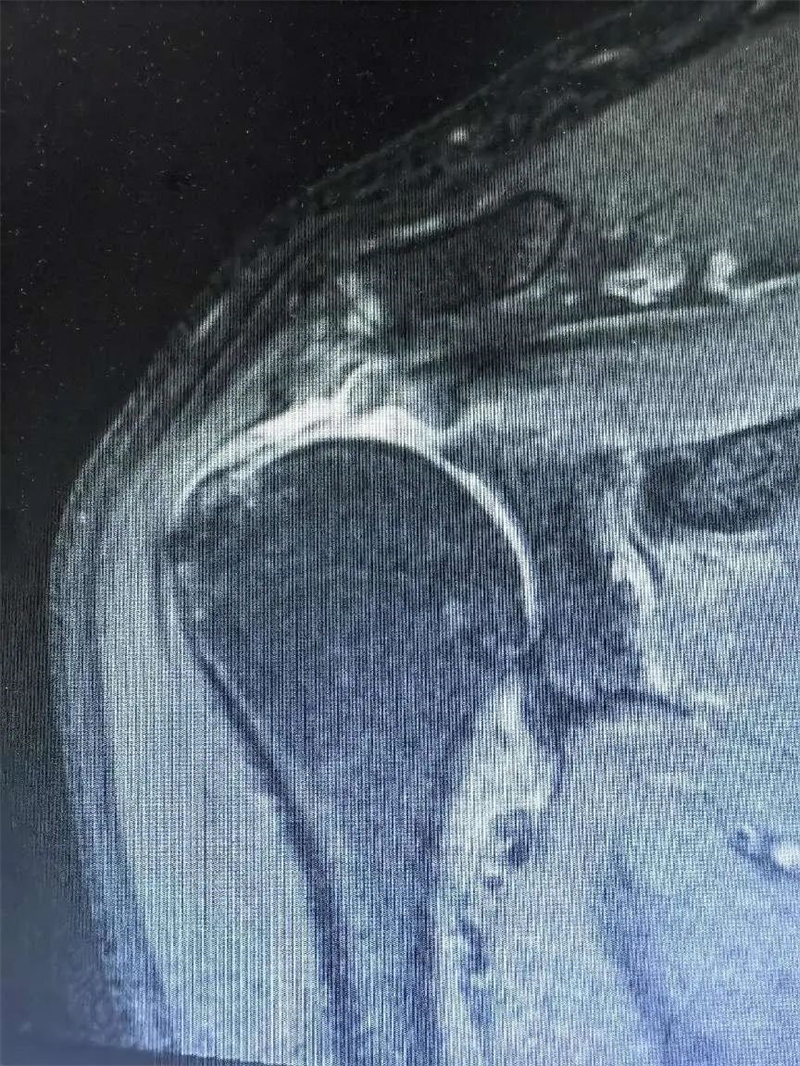

10月15日,秦皇岛41岁的张姓患者因骑车时摔伤导致右肩活动受限十余天,通过多方了解来到军工医院运动医学科就诊。运动医学科薛朝亚主任和孙超主治医师详细询问患者情况及症状。患者由于受伤以来不敢活动,继发肩关节粘连,肩关节活动度差,关节间隙不好,肩袖撕裂回缩严重,已经从正常的肱骨大结节回缩至肩胛盂上,合并肱二头肌腱脱位、肩胛下肌完全撕裂,回缩粘连,属于复杂型巨大肩袖撕裂。

肩袖是包绕在肱骨头周围的一组肌腱复合体,包括冈上肌腱、冈下肌腱、肩胛下肌腱和小圆肌腱,这些肌腱将肱骨头稳定于肩胛盂上,对维持肩关节的稳定和肩关节活动起着极其重要的作用。其中冈上肌主要负责上抬肩关节、和下压肱骨头的作用,撕裂后主要表现为疼痛和抬肩无力,肩胛下肌主要负责肩关节内旋,损伤后主要表现为内旋无力与疼痛,患者因肩袖损伤后继发关节粘连,需手术治疗。运动医学科医疗团队经术前讨论后制定手术方案,孙超医生与患者及家属详细沟通,确定手术治疗。 术前准备完毕,手术开始。医生将患者肩关节囊、肌腱松解后分别行肩胛下肌修复、肱二头肌腱固定术与冈上肌修复术。在兄弟科室的配合下,手术取得圆满成功。